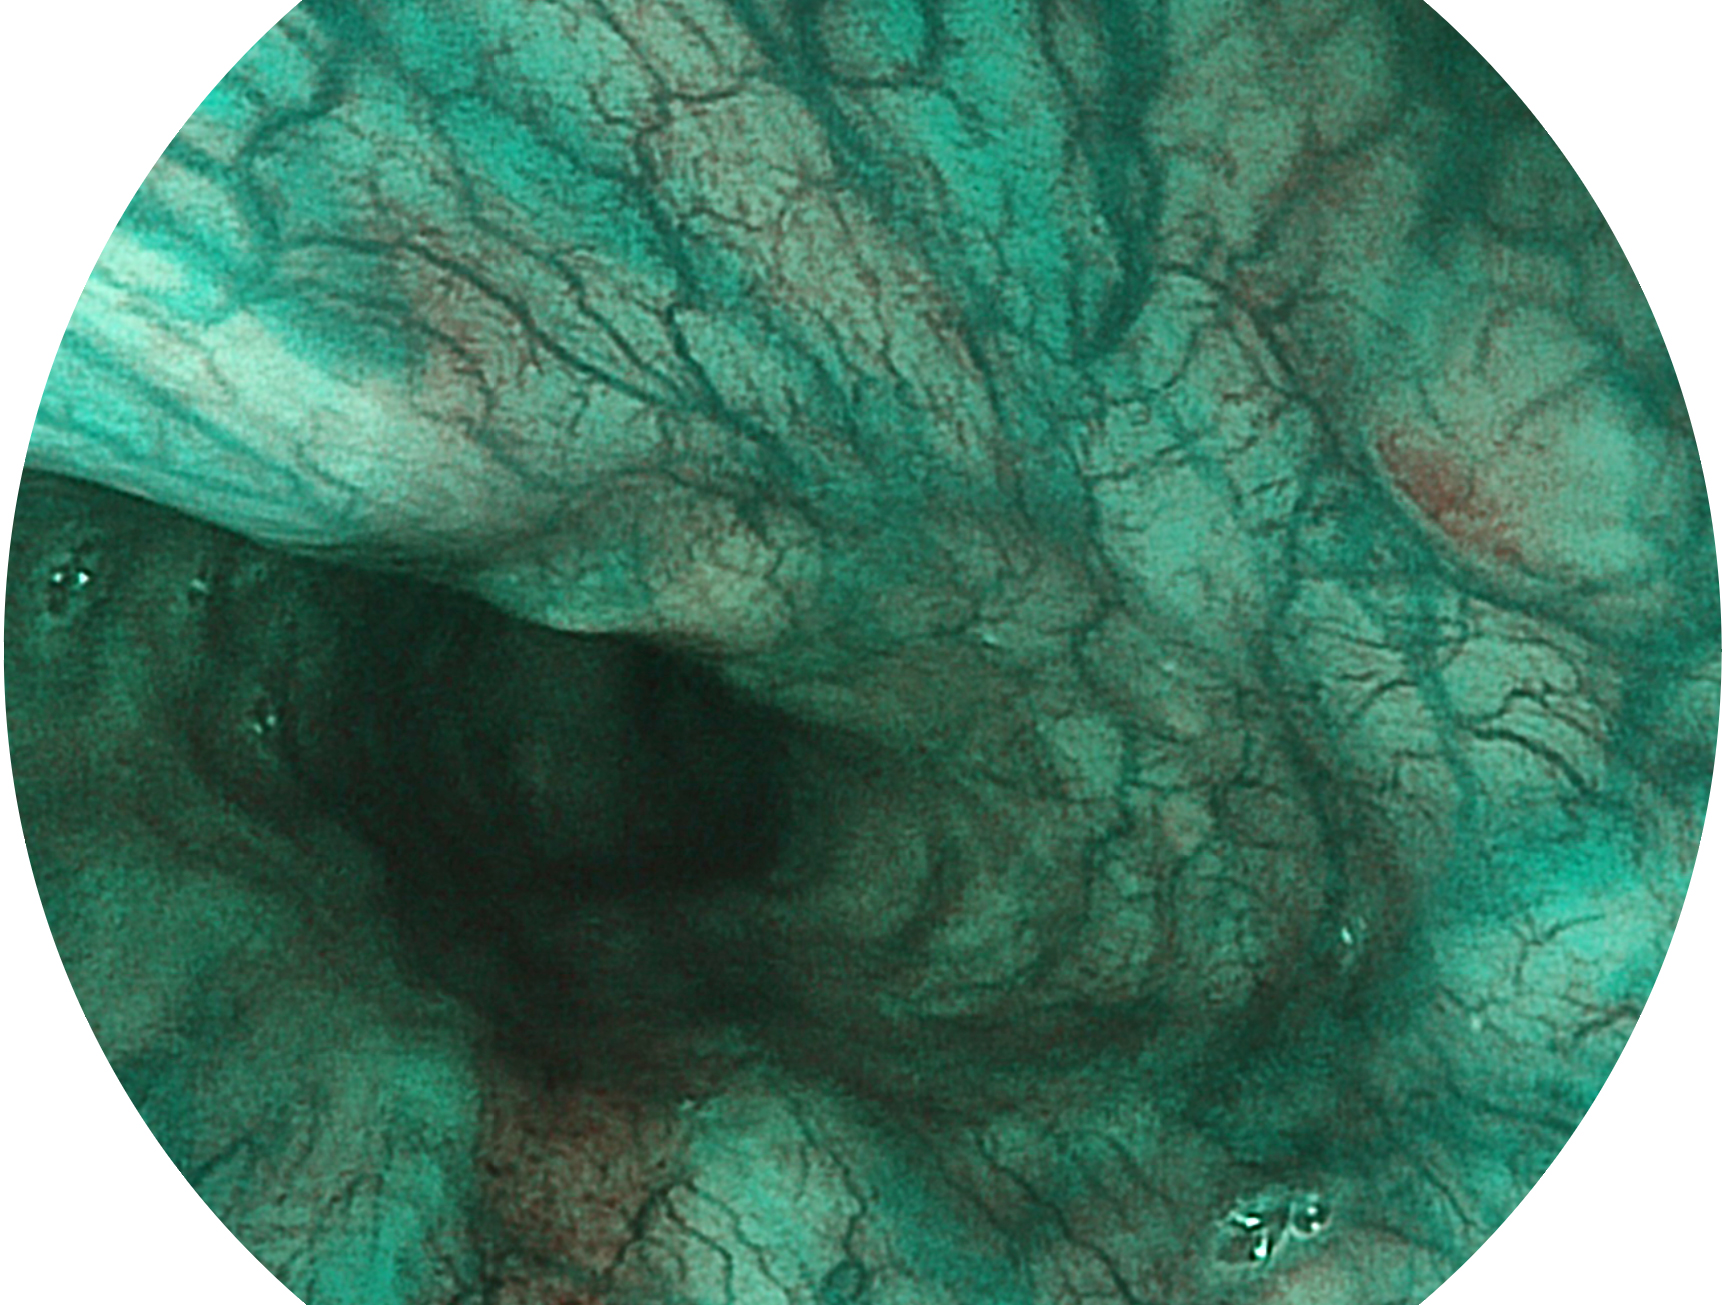

開立新開發(fā)的內(nèi)鏡染色技術(shù),主要是基于多波長LED 光源的開發(fā),VLS-55Q 四波長LED 光源是由四個(gè)不同顏色的LED光按照相應(yīng)照明模式所規(guī)定的特定發(fā)光比例進(jìn)行合束后形成,合束后形成的照明光的光譜由紅光、綠光、藍(lán)光及藍(lán)紫光這四個(gè)不同的波段范圍構(gòu)成。具有更高光譜自由度,通過光譜比例的控制,實(shí)現(xiàn)了聚譜成像技術(shù),英文全稱為“Spectral Focused Imaging, SFI”,縮寫為“SFI”和光電復(fù)合染色成像技術(shù),英文全稱為“Versatile Intelligent Staining Technology, VIST”,縮寫為“VIST”。